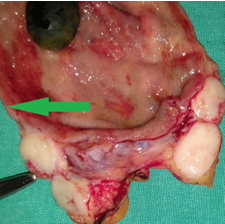

The two metastatic foci causing stenosis and bowel obstruction are clearly visible (Courtesy Dr. V. Penopoulos)

After opening the specimen, the metastatic foci are clearly visible (Courtesy Dr. V. Penopoulos)